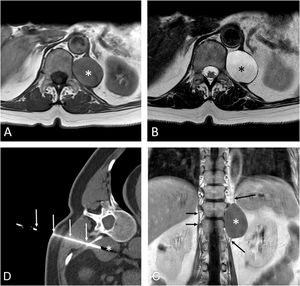

(A and B) Axial T1-weighted (A) and T2-weighted (B) MR images show a well-defined retroperitoneal lesion (asterisk) involving the left crus of the diaphragm. (C) Coronal T1-weighted MR image following the administration of iv contrast confirms the cystic nature of the mass (lack of enhancement) and better shows the relationship of the lesion with the crus of the left hemidiaphragm (long arrows); note the normal appearance of the right crus of the diaphragm (short arrows). (D) Axial CT image (mediastinal window) shows the fine-needle aspiration procedure (arrows) of the lesion (asterisk).

A 58-year-old woman complained of chest discomfort. A computed tomography (CT) identified a low-attenuation retrocrural soft-tissue lesion at the level of T12, suggesting the diagnosis of a nerve sheath tumor or a focus of extramedullary hematopoiesis. Magnetic resonance imaging (MRI) showed a cystic nature, with a differential diagnosis that included a lymphangioma/lymphocele, a cystic nerve sheath tumor, or a chronic hematoma (Fig. 1A–D). A CT-guided fine-needle aspiration (FNA) of the lesion was performed (Fig. 1E), revealing the presence of benign-appearing ciliated columnar epithelial cells within a mucinous background. Based on these findings, a diagnosis of bronchogenic cyst (BC) was made. The patient was referred to thoracic surgery but, given that the cyst had been partially evacuated and that the symptoms had subsided, conservative management was decided.